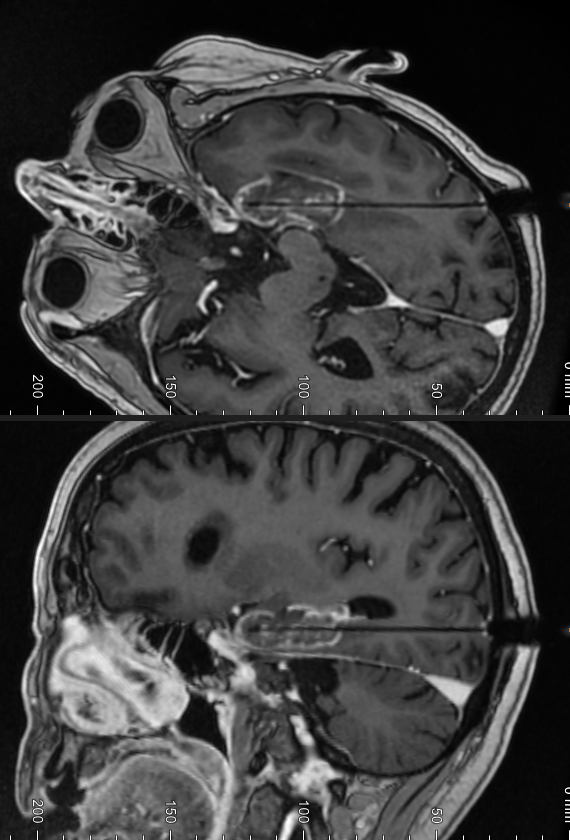

Et vandkølet laserfiber indføres stereotaktisk i hjernevævet. (Samme teknik som ved Stereotaktisk biopsi - Patientinformation) Laserlyset stråler ud til siderne i det yderste stykke af fiberet og absorberes i hjernevævet omkring, hvilket resulterer i en stigning i temperatur. Temperaturen når 80-90 grader omkring fiberet og aftager gradvist udefter. Ved temperaturer over 70 grader sker der vævskoagulation, og proteiner denaturerer, hvilket medfører øjeblikkelig destruktion af vævet. Ved temperaturer mellem 44 og 70 grader afhænger ablationen af eksponeringstiden.

Temperaturen måles i realtid i en MR-scanner, hvor et termografisk billede viser temperaturen i forhold til vævet og computeren hjælper med at estimere udbredelsen af den varige skade. En cylindrisk ablation med en diameter på op til 18 mm kan opnås, mens længden af ablationen er ubegrænset, da laserfiberet kan retraheres inden i kølekateteret. Dybden af måleområdet er af mindre betydning.

LITT er således et effektivt alternativ til åben resektion ved mindre, eventuelt aflange epileptogene zoner i dybden. For eksempel kan en selektiv hippocampus-ablation opnås ved at indføre kateteret langs hippocampus.